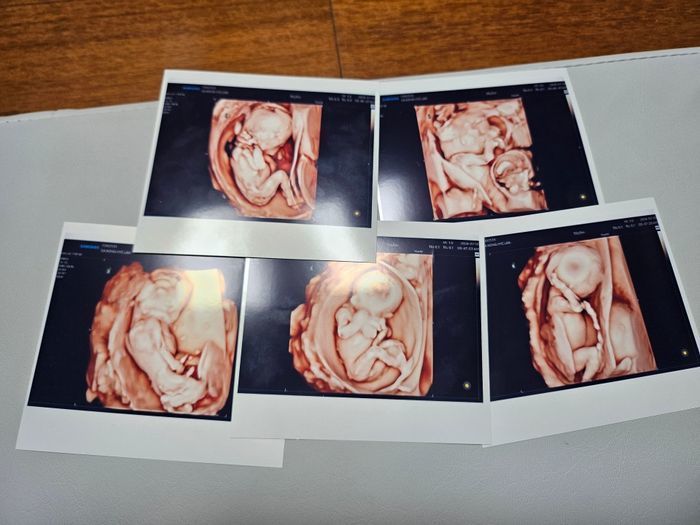

다섯쌍둥이의 초음파 사진. ⓒ서울성모병원

국내에서 처음으로 자연임신 다섯쌍둥이가 탄생했다. 3년 전 국내에서 다섯쌍둥이가 태어나 화제가 된 적이 있지만 자연임신으로 탄생한 것은 이번이 처음이다.